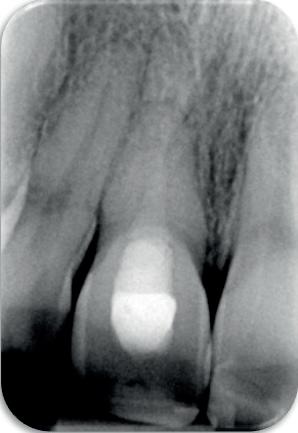

14-16. Patiënt presenteerde zich met een forse zwelling en botverlies rondom het implantaat.

17. Verwijderen van de tijdelijke kroon.

18. Explantatie van het implantaat.

19. Curettage van de alveole in combinatie met curettage totdat er geen exsudaat meer was.

derprepareerde ik de osteotomie. Dit betekende dat ik een iets te smal implantaatbed creëerde, in de hoop dat het implantaat stevig in het bot verankerd zou worden.

Op papier leek dit een logische stap: het MegaGen AnyRidge-implantaat dat ik koos, gaf me een stabiliteit van 60Ncm—een cijfer dat vertrouwen gaf in immediaat belasten. Maar in mijn enthousiasme had ik onvoldoende rekening gehouden met de biologische gevolgen van overmatige compressie.

Door de te hoge druk op het omringende bot verminderde daarin de doorbloeding, wat leidde tot een verhoogd risico op botnecrose. Dit was geen fout van abutmentkeuze of occlusie; dit was puur het gevolg van mijn drang naar optimale stabiliteit en de wens om het implantaat direct te belasten, onder invloed van patiëntdruk.

Het kantelpunt: de patiënt komt terug (afbeelding 14-16)

De patiënt meldde zich opnieuw in de praktijk met klachten: pijn, zwelling en een duidelijke intraorale infectie. Bij inspectie zag ik direct een probleemhet ging om een klassiek beeld van peri-implantair botverlies met een abces. Dit patroon van botverlies en infectie spiegelde sterk de gevolgen van thermische trauma.

Op de röntgenfoto’s zag ik wat ik al vreesde: er was botresorptie rond het implantaat. De zachte weefsels waren ontstoken en het implantaat vertoonde teke-

nen van mobiliteit. Op dat moment wist ik precies wat er was misgegaan.

Dit was geen kwestie van een verkeerde occlusie of een slecht gekozen abutment. Dit was een puur biologisch probleem, veroorzaakt door mijn onderpreparatie van de osteotomie en de daarmee gepaard gaande botnecrose of compressie. Mijn streven naar immediaat belasten had me verblind, en ik had een fundamentele regel van de implantologie genegeerd: bot moet kunnen ademen. Op dat moment had ik geen andere keuze dan de situatie te herstellen.